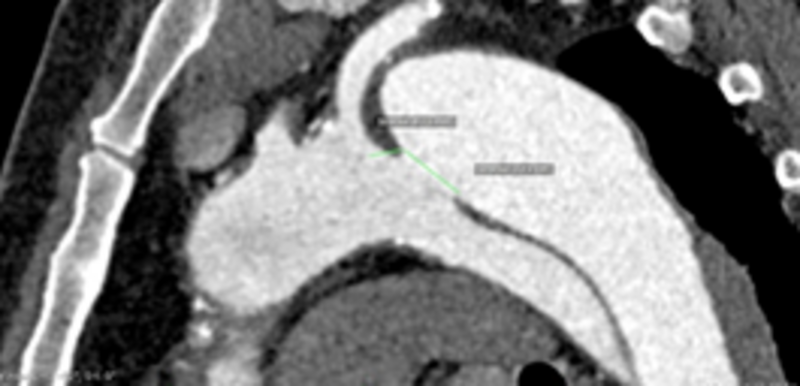

Bei einer Dissektion der Hauptschlagader (Aorta) kommt es zu Einrissen in der dreischichtigen Gefäßwand. Blut „wühlt“ sich in die Wandschichten und verursacht einen Blutfluss in der Aortenwand. In der Aorta entsteht so neben dem wahren, ein falsches, mit Blut gefülltes Lumen.

Dieses Einreißen der Aortenwand ist ein dramatisches Ereignis. Es kann den aufsteigenden Teil der Aorta direkt hinter dem Herzen (Typ A-Dissektion) und hinter dem Aortenbogen den weiteren Verlauf der Hauptschlagader (Typ B-Dissektion) betreffen.

Im Folgenden wird die Typ B-Dissektion in der Einteilung nach Stanford angesprochen. Die Diagnostik erfolgt mittels:

• Computertomographie (CT)